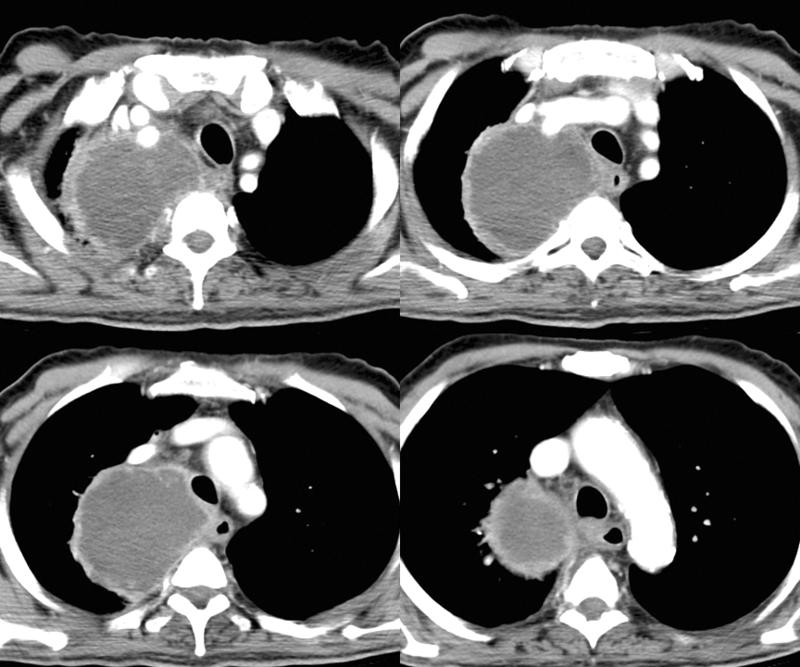

Gallery Lung Cancer Nodules & Masses 15b

15b